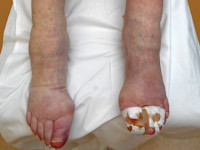

Calciphylaxis cutisCalciphylaxis cutis is een zeldzame aandoening

waarbij grillige en zeer pijnlijke ulcera ontstaan door

calciumdeposities in

kleine en medium-size arteriën. De kalkafzettingen kunnen in een huidbiopt

stelsel is verkalkt en zichtbaar, alsof het een contrastfoto was. De huid

die werd voorzien door het afgesloten arterietakje sterft af, hierdoor is de

aandoening zeer pijnlijk. De prognose is slecht en de sterfte is hoog, omdat

![Calciphylaxis cutis bij nierinsufficiëntie en secundaire hyperparathyreoïdie (click on photo to enlarge) [source: www.huidziekten.nl] Calciphylaxis cutis bij nierinsufficiëntie en secundaire hyperparathyreoïdie](../../../images/calciphylaxis-1z.jpg) |

![Calciphylaxis cutis bij nierinsufficiëntie en secundaire hyperparathyreoïdie (click on photo to enlarge) [source: www.huidziekten.nl] Calciphylaxis cutis bij nierinsufficiëntie en secundaire hyperparathyreoïdie](../../../images/calciphylaxis-2z.jpg) |

| calciphylaxis cutis |

calciphylaxis cutis |